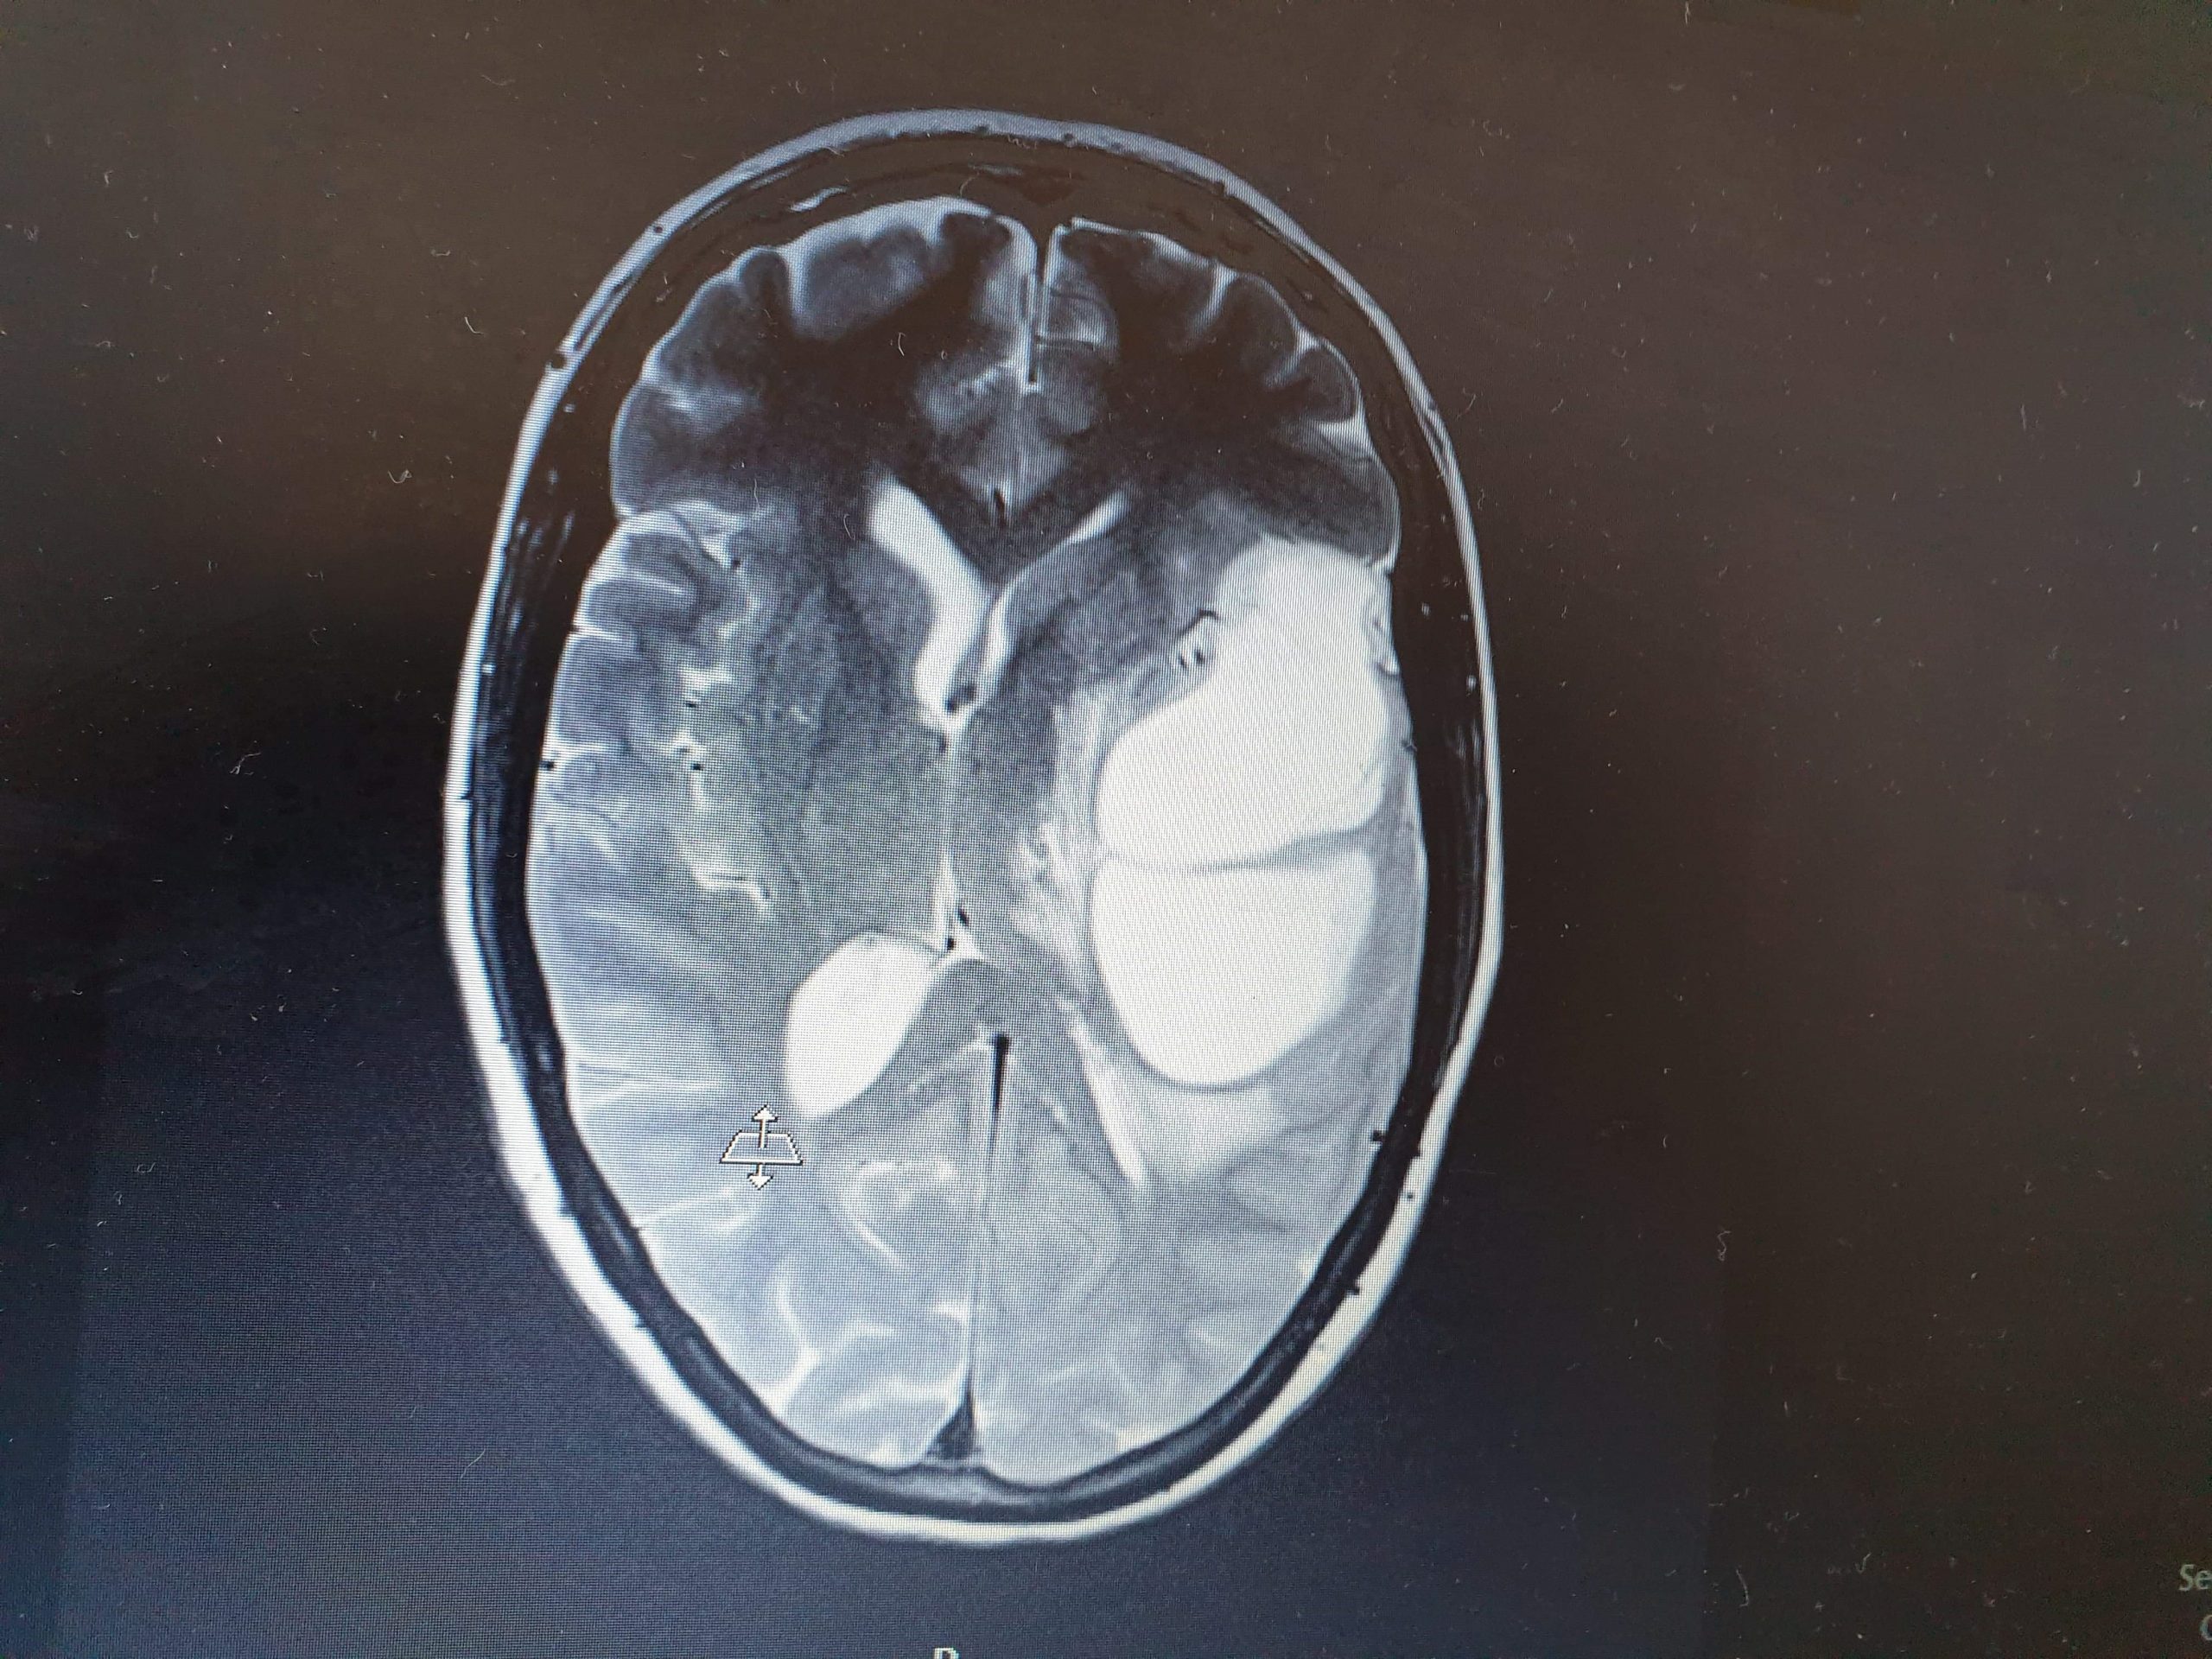

By June 2019, it was like he’d always been one of the gang. But Mum had begun acting strangely. She was dizzy, forgetful... The doctors diagnosed her with stress and exhaustion. But then she ended up in hospital. Confused, she didn’t know who or where she was. The doctors thought it might be a stroke. But after an MRI scan, they called us all in.

‘I need to show you something,’ a doctor said. Staring at the big, white blob on the scan, I was in shock. It was a brain tumour. On 4 July, Mum underwent surgery to remove 70 per cent of the tumour. But a biopsy later showed that it was a highly aggressive glioblastoma.